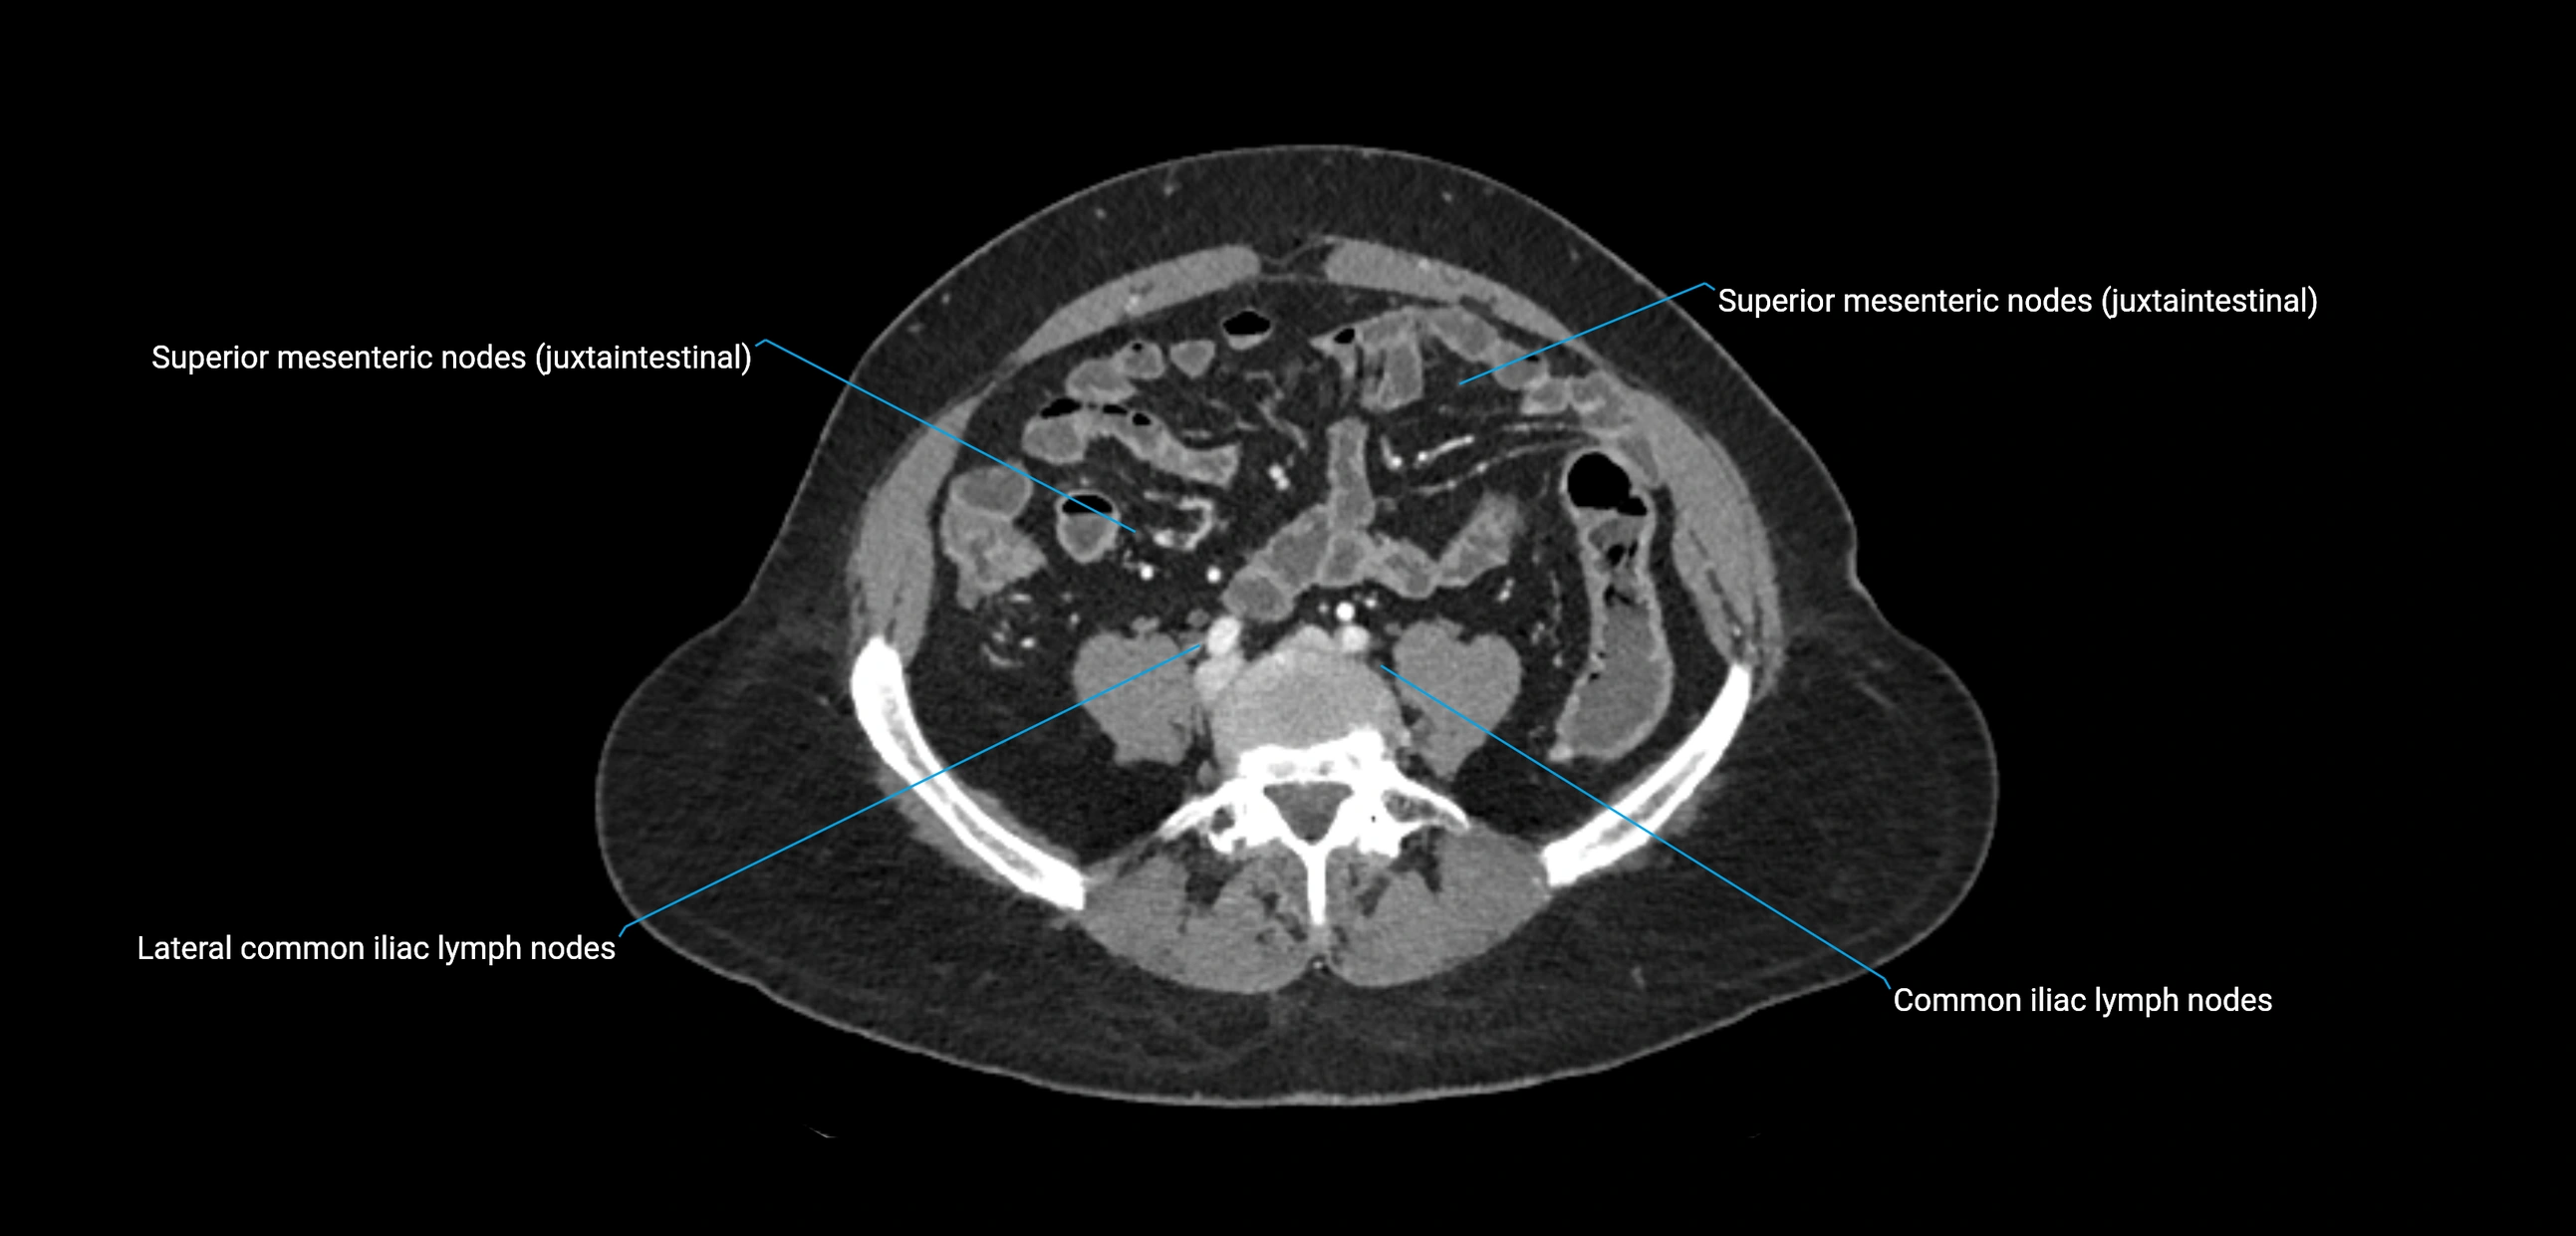

CT image

image